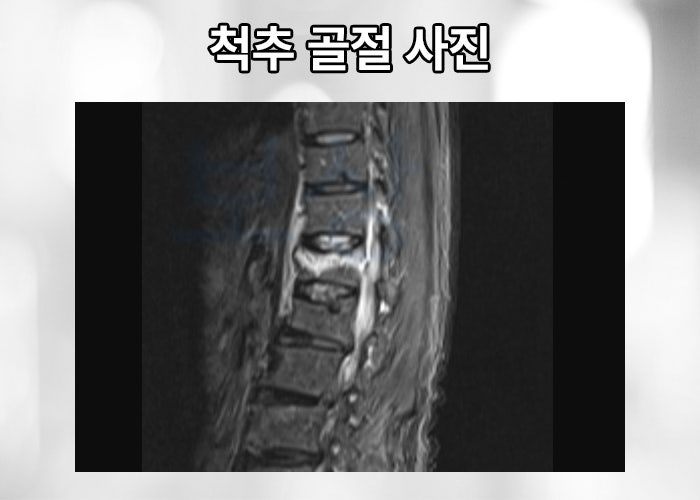

위 mri 촬영한 사진을 보시면 유독 위 아래의 추체와 다르게 눌려있는 척추체가 보이는데요, 위 사진은 요추 1번 압박골절 진단받은 환자분의 영상 사진입니다. 의뢰인은 다행히 골밀도가 좋은 편에 속하고 골절의 정도와 형태가 심하지 않아 TLSO 허리 보조기 착용하며 일정 기간 요양하는 비수술적 보존 치료 시행하게 되었습니다.

하지만 한번 골절된 척추체는 다시 원통모양으로 복귀되지 않습니다. 또한 점점 무너져 내려 척추의 전만, 후만의 기형을 야기하게 됩니다. 척추 압박골절로 일정 기간이 지나 괜찮아졌다고 해도 본래 척추 만곡에 기형이 발생할 수 있기 때문에 실비, 입원비, 골절 진단금 뿐만 아니라 후유장해 보상도 알아보아야 합니다.